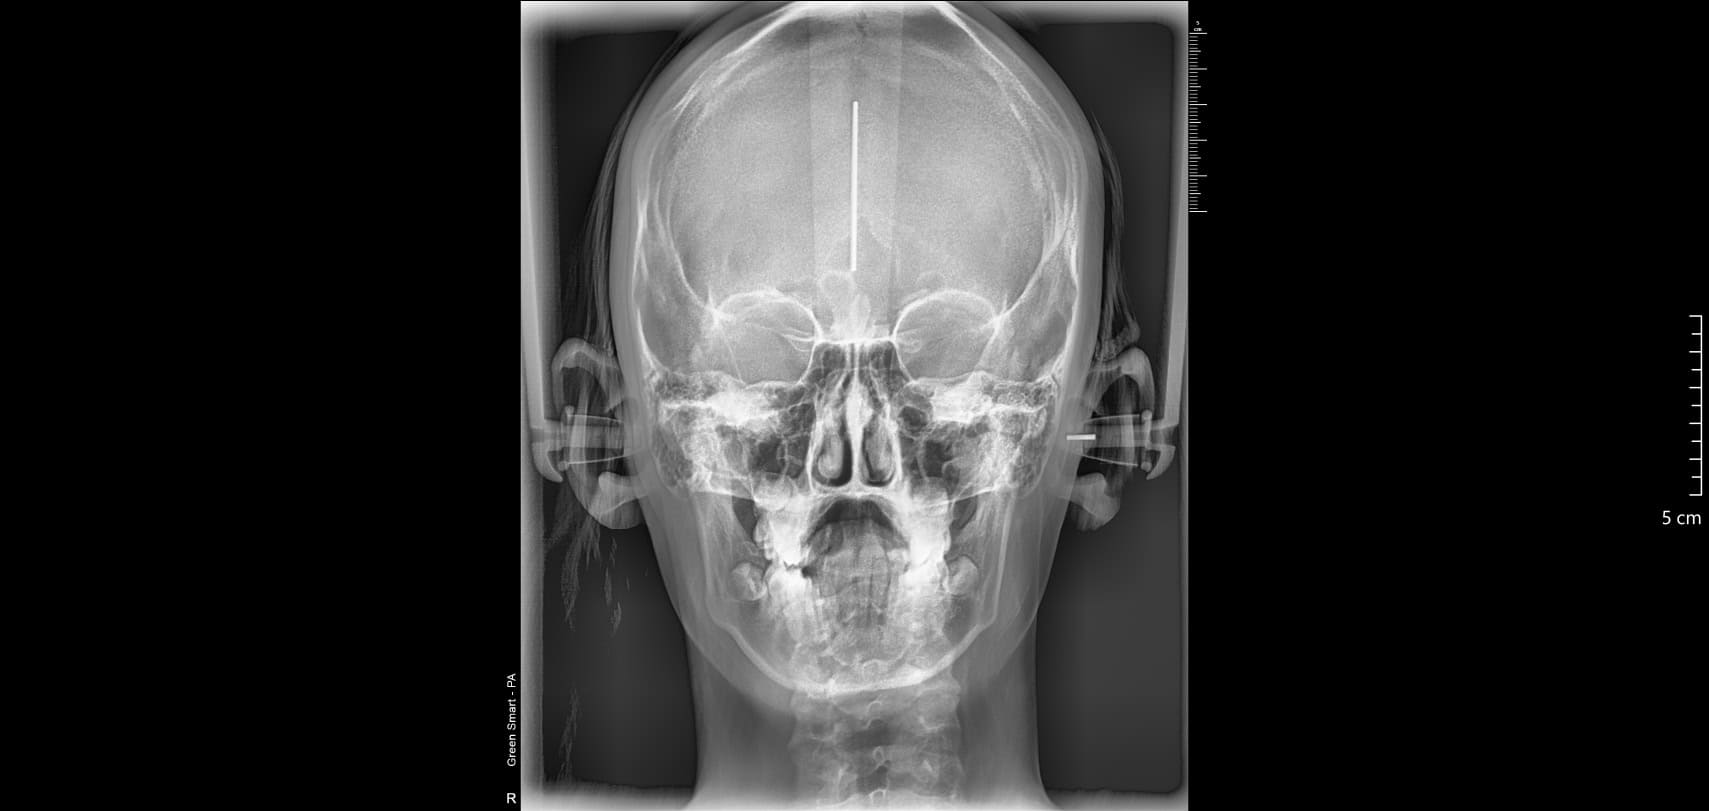

les télécrânes pour l'orthodontie: